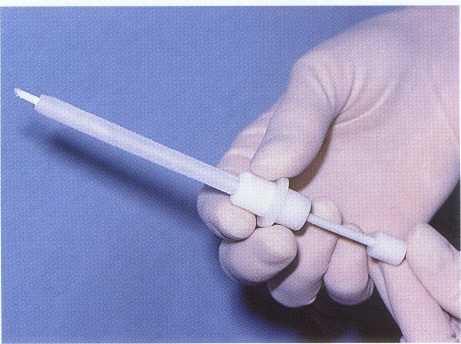

FIGURE 1-2

C02 snow is an excellent method of thermal testing because it provides a temperature of -50° C and transforms from a solid to a gaseous state, eliminating the potential for stimulation of adjacent teeth.

THERMAL TESTING. Thermal sensitivity is a common chief complaint in pulp pathosis. Testing with hot and cold identifies the tooth and is instrumental in determining whether the pulp is normal or inflamed. Cold testing is usually performed first. Carbon diox-

ide, or C02 (Figures 1-2 and 1-3), ethyl chloride, dichlorodifluoromethane (Figure 1-4), and ice sticks (Figure 1-5) are frequently used to apply cold to teeth. These tests have been shown to be safe and do not cause damage to the pulp8,9 or enamel.10 Patients should be advised of the testing method and expected sensations. The testing should begin on a normal "control" tooth (usually of the same tooth group or type) to educate the patient regarding what to expect from the test, determine whether the test will provoke a response (validating the use of the